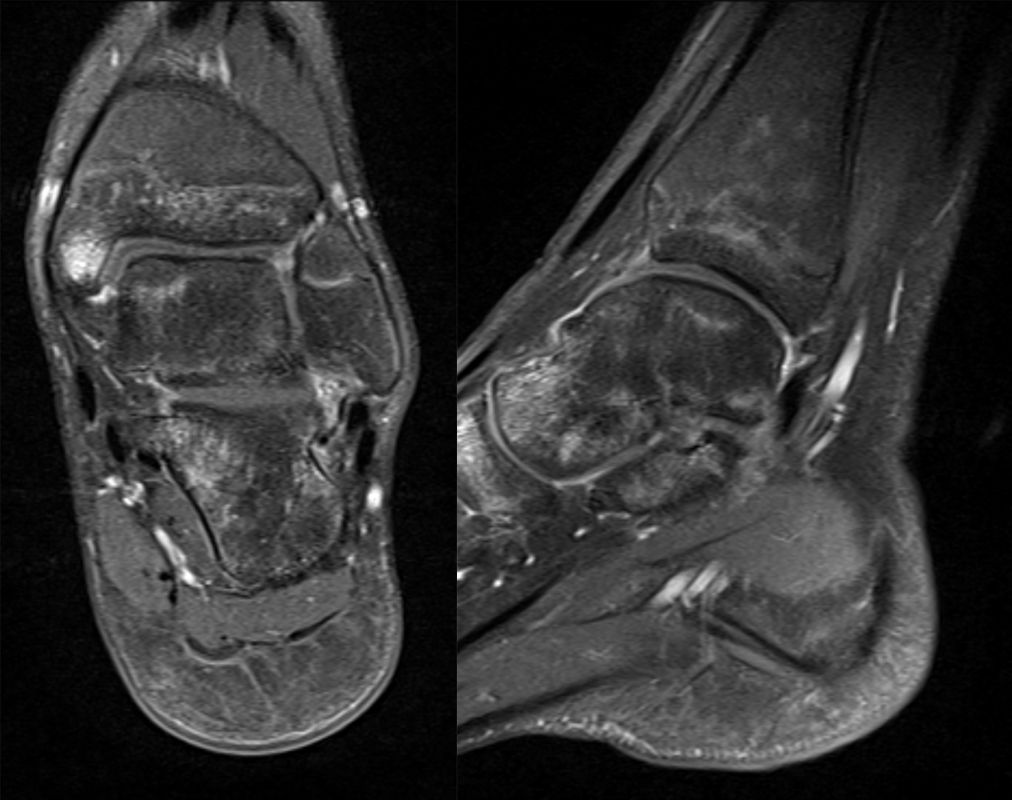

MRT

Die Kernspintomographie hat ihre Stärke in der Darstellung von Weichteilverletzungen. Insbesondere Verletzungen der Wachstumsfuge, des Periosts und der Bänder lassen sich gut visualisieren. Nachteilig ist die Untersuchungsdauer von 20-30 Minuten. Bleibt das Kind während dieser Zeit nicht ruhig liegen, kommt es zu Bewegungsartefakten, welche die Beurteilbarkeit der Bilder beeinträchtigen.

Fugengelenkfrakturen treten typischerweise vor dem 10. Lebensjahr auf, in einer Phase, in welcher die Wachstumsfugen noch weit offen sind. Dieser Frakturtyp betrifft fast ausschließlich den medialen Malleolus. Laterale Frakturen sind extrem selten, teilweise kommt es zu lateralen Bandverletzungen oder Fugenschaftfrakturen der distalen Fibula. Die Frakturlinie verläuft in einer Verlängerungslinie von der medialen Taluskante nach proximal. Häufig stellen sich Verletzungen des Innenknöchels im Röntgenbild schlechter dar, insbesondere wenn die Aufnahmen verdreht sind oder die Ebene der Fraktur bei geringer Dislokation verkippt zur Röntgenebene liegt. Besteht klinisch der geringste Hinweis auf eine Verletzung des Innenknöchels, muss aufgrund der Tragweite der Verletzung durch entsprechende Aufnahmen gegebenenfalls auch Schnittbildverfahren die Verletzung sicher diagnostiziert oder ausgeschlossen werden (Abb. 15).